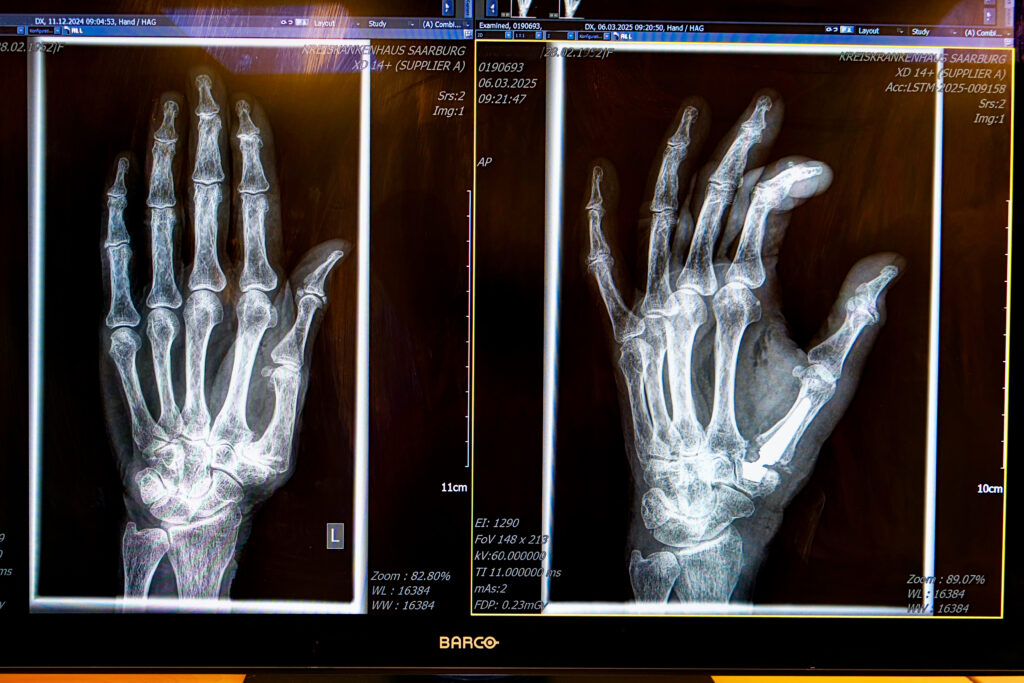

Rhizarthrose / Daumensattelgelenksarthrose

Die Rhizarthrose ist die medizinische Bezeichnung für die Arthrose des untersten Daumengelenks.